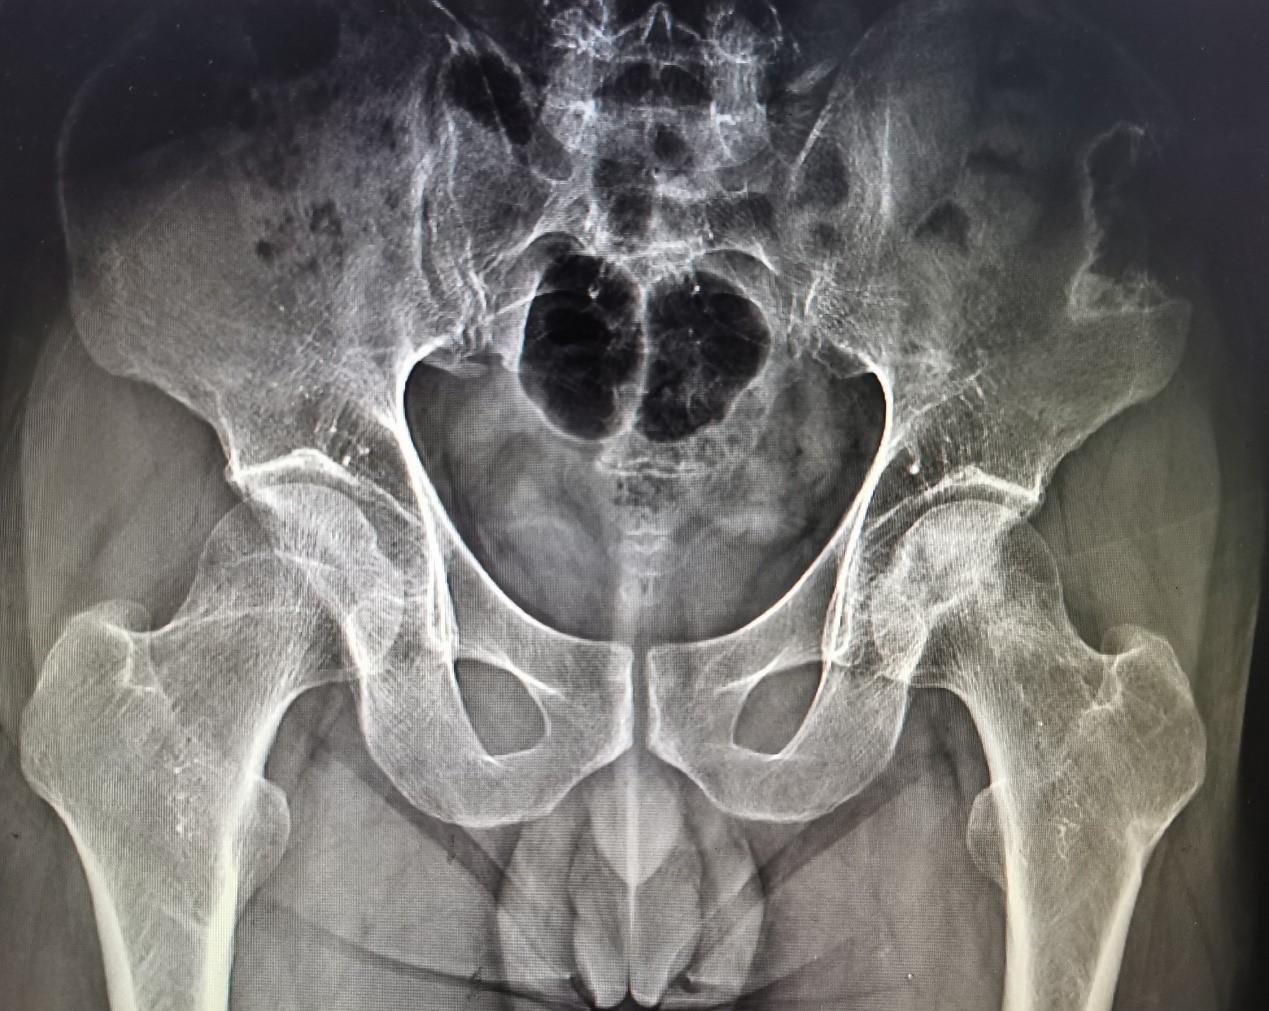

股骨颈骨折术前